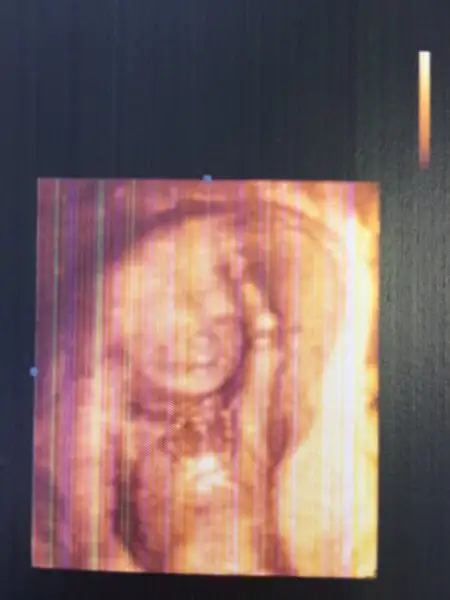

Güleç oğlum mutlu oğlum Cihangir :)